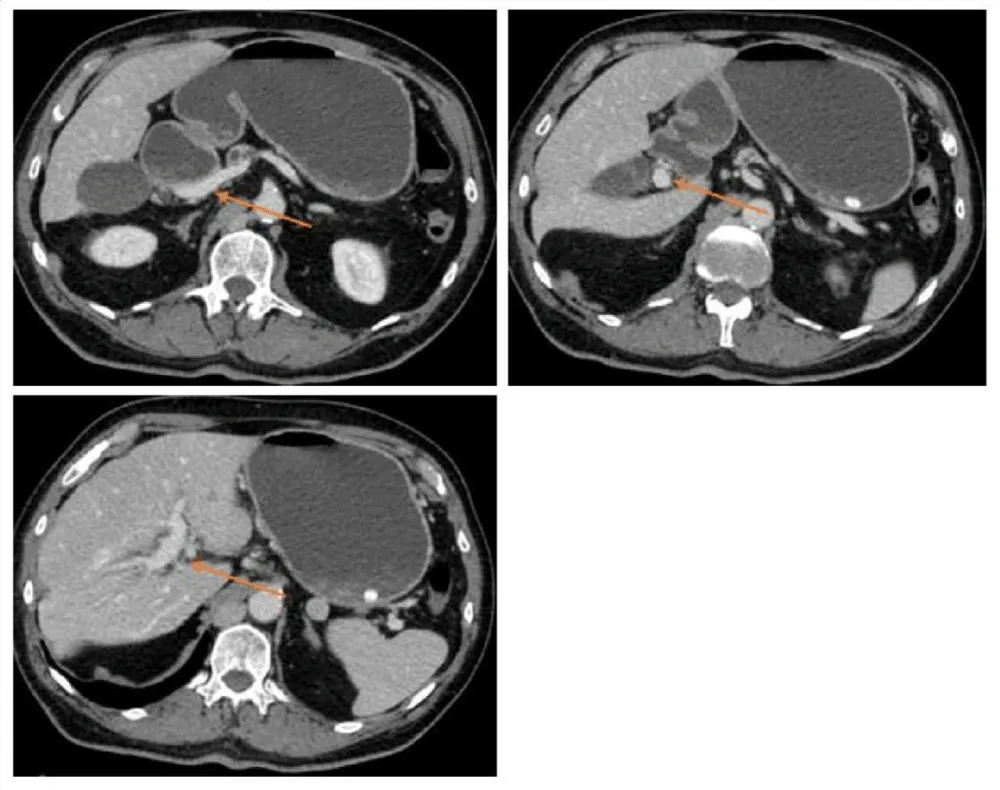

Duplicated portal vein:

1. portal vein in regular position, formed from the inferior mesenteric vein and the splenic vein, supplying segment III, IVb, and V (Figures 1,2).

2. portal vein, which forms from the superior mesenteric vein entering the liver in the ligamentum teres hepatis, supplying the other segments (Figure 3).

3. Both portal veins are connected extrahepatically via a 3 cm anastomotic vein (Figure 4).

Figure 2: CT scan presenting the first portal vein forming from V. mesenterica inferior and V. lienalis.

Figure 3: CT scan presenting a second portal vein forming from V. mesenterica superior, entering the Liver via the ligament. Teres hepatis.

Figure 4: CT scan presenting the extrahepatic interportal anastomotic vein.